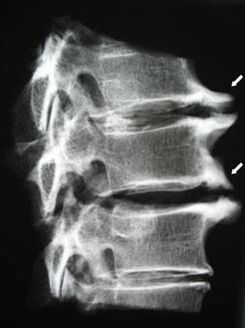

| Zervikal Osteochondrose | D’Erscheinung vu pathologesche Verännerungen an engem oder méi Spinalbewegungssegmenter. Behënnerte Spinal Mobilitéit, Entwécklung vu myofasciale Schmerzsyndromen a Prise vu Spinalwurzelen | Péng, Parästhesie a Motorstéierungen an der Gebärmutterhalsregioun, déi sech op d’Réck vum Kapp an den ieweschte Glieder verbreet. Detektioun vu charakteristesche Verännerungen an der Wirbelsäule op MRI a Röntgenbilder (Osteophyten, ofgeholl Distanz tëscht Wirbelen, Zeeche vu Schied un intervertebrale Gelenker) |

An den initialen Etappen gëtt Osteochondrose mat MRI festgestallt. Spéider kann Pathologie diagnostizéiert ginn duerch Radiographie. Op Röntgenbilder vun der Gebärmutterhalskierch gëtt eng Ofsenkung vun der Distanz tëscht de Wirbelen, pathologesch Verännerungen an de Facettegelenken an Osteophytose bemierkbar.